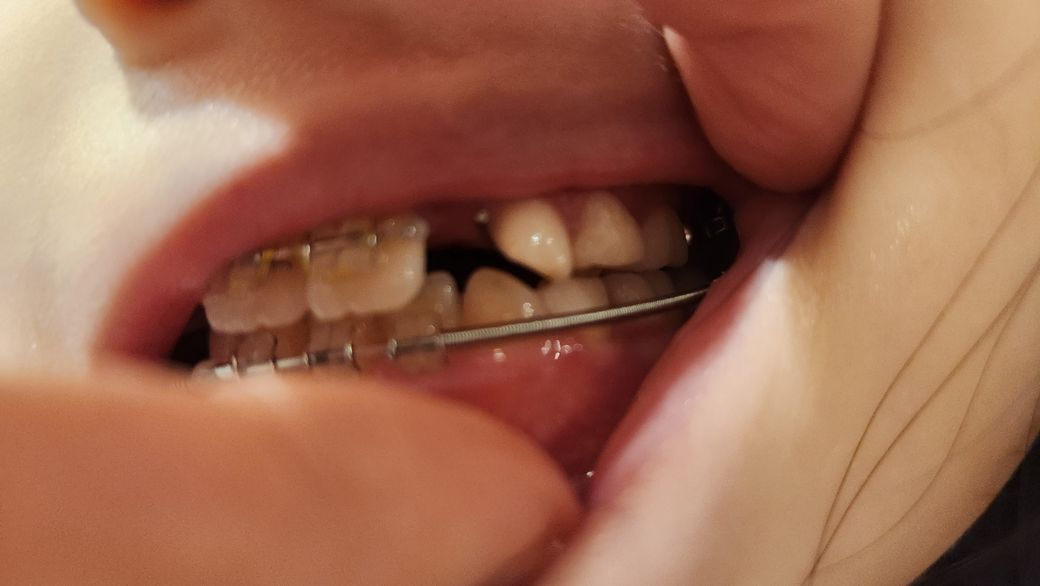

그런데 사진에서 보면 오른쪽 위아래 어금니의 교합이 전혀 맞지 않아요

왼쪽은 좀 맞는 듯 보이는데

제가 봤을때는 오른쪽은 심하고 왼쪽은 덜한것 같은데

교정과에서는 둘이 똑같고

교합이 맞지 않은 현상태도 괜찮다고 하더라고요

제가 이대로 교정기를 빼도 되는 거냐 하니

지금 오버해서 늘려놓은 상태고

교정기를 빼면 좀 줄어들것 이라고 했어요

어금니 교합이 맞던 아이를 상악만 오버해서 늘려서 교합이 안맞게 만들고 교정기를 빼면 다시 좀 줄어든다는데 ....

제 상식으로는 그럼 위 아래 다 늘려서 교합이 맞게 했어야 하는거 아닌가 싶어요

아래 오른쪽 영구치 어금니에 교정기가 부착되어 있는데 점점 옆으로 누워지고 있어요

이것도 교정과에서는 괜찮다고 하더라고요